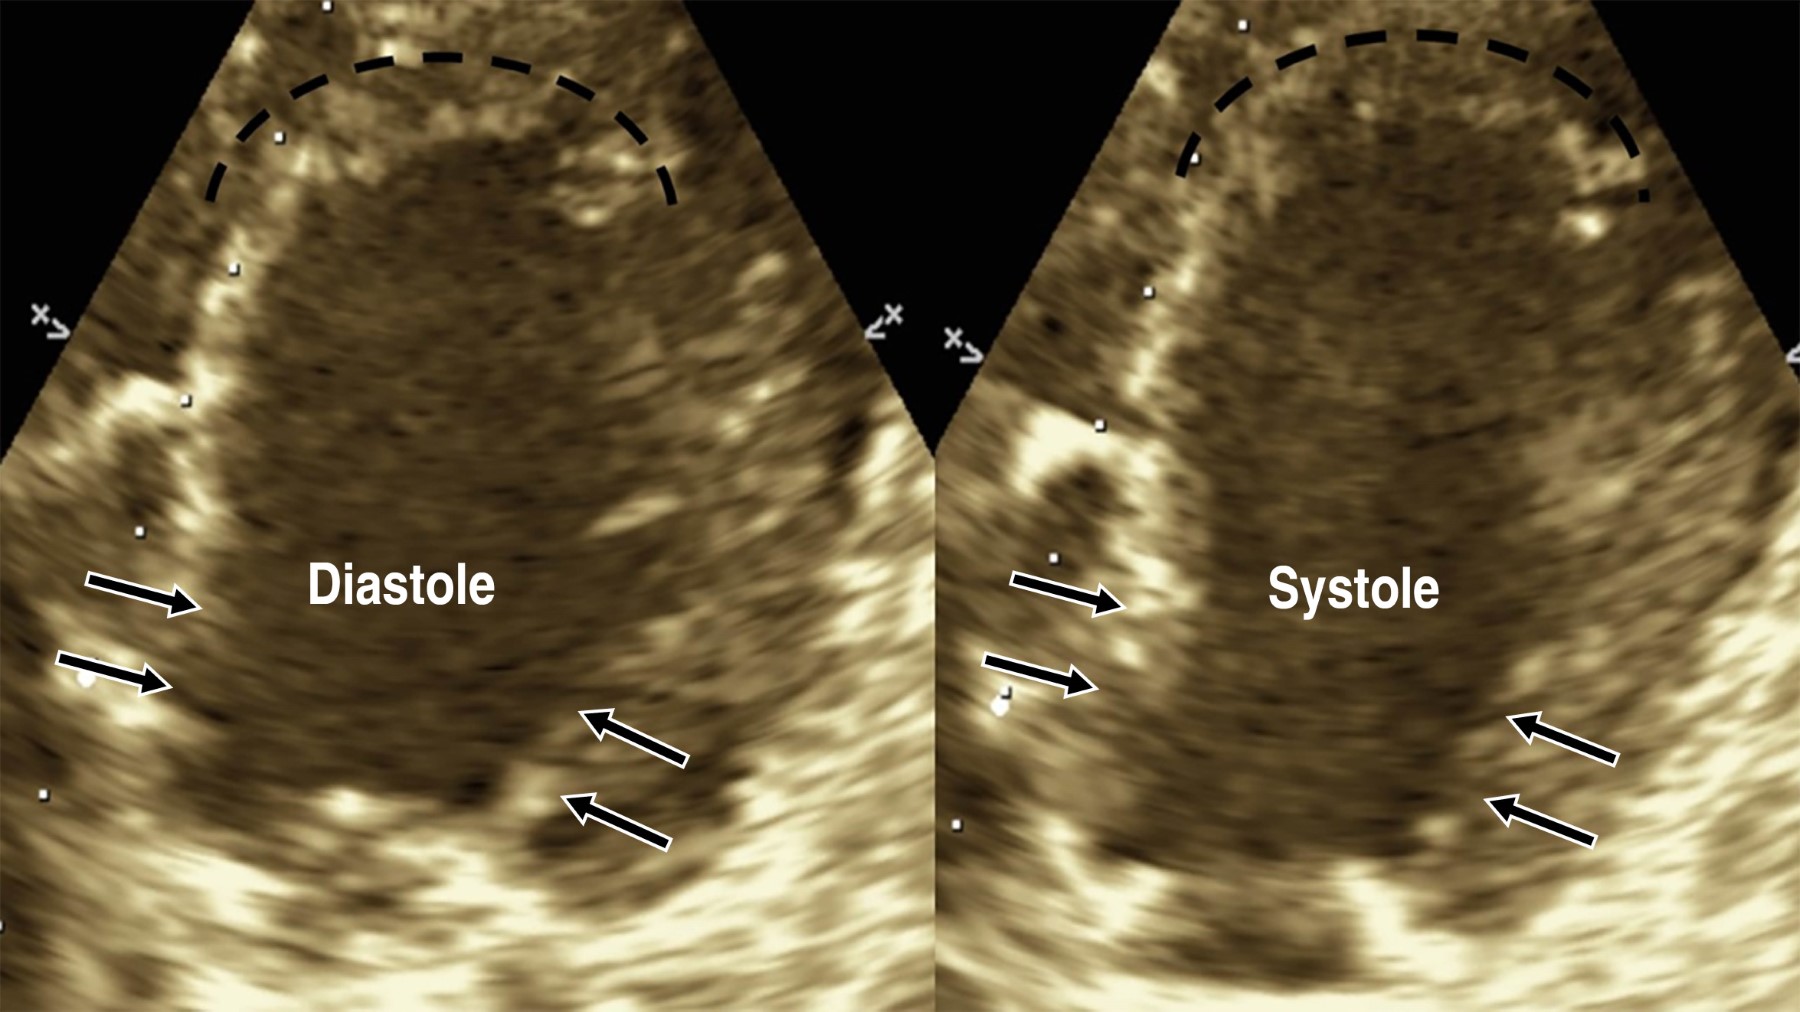

Table 1 shows the patients' origin and demographics. Table 2 shows the basal patient's characteristics, and Table 3 displays the diagnostic angiography and outcomes; Figure 1 displays the Killip-Kimbal class progress and Figure 2 the ejection fraction; Figure 3 shows an example of the echocardiographic in one of our patients, showing the characteristic apical ballooning on dotted lines and the typical basal contractility shown by the arrows.

Figure 3